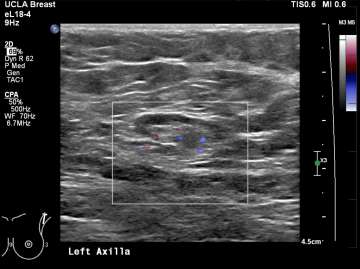

Ultrasound is the best modality for characterizing lymph nodes allowing for evaluation of shape, cortical thickness and presence or absence of fatty hilum. On ultrasound, normal axillary lymph nodes have an oval or lobulated shape with a preserved fatty hilum and cortical thickness less than 3 mm (figure 2). The echogenic hilum has arterial flow which can be assessed using color doppler imaging.